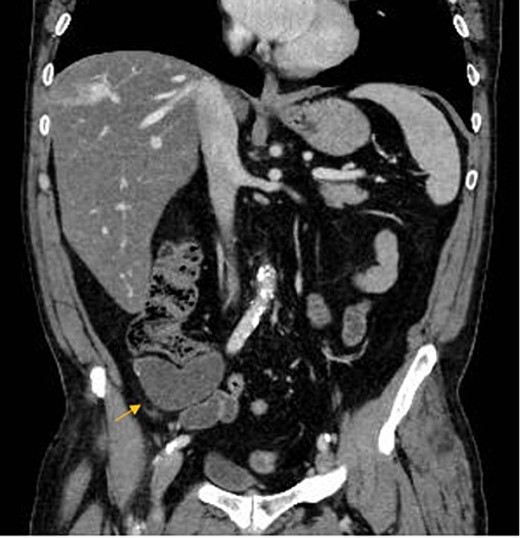

A 67-year-old man presented to our emergency department for abdominal pain occurred about 3 days ago. Past medical history included ischemic heart disease, type II diabetes mellitus, chronic obstructive pulmonary disease, obstructive sleep apnea syndrome, smoking. No history of previous surgery. Laboratory markers showed hemoglobin 13.3 g/dL, leukocytes 8.9 × 109/L, C-reactive protein 11 mg/L. CT scan detected a 7.5 × 3.2 cm diameter suprafluid tubular neoformation in continuity with the caecal fundus, compatible with AM (Figs 1 and 2). A contextual focal wall thickening of 1.1 × 0.5 cm in diameter with slender calcifications was also appreciated. No repetitive parenchymal or peritoneal nodularity had been documented. Colonoscopy showed a rosy and regular mucosa in all colic segments explored up to the cecum, with no detectable pathological lesions.